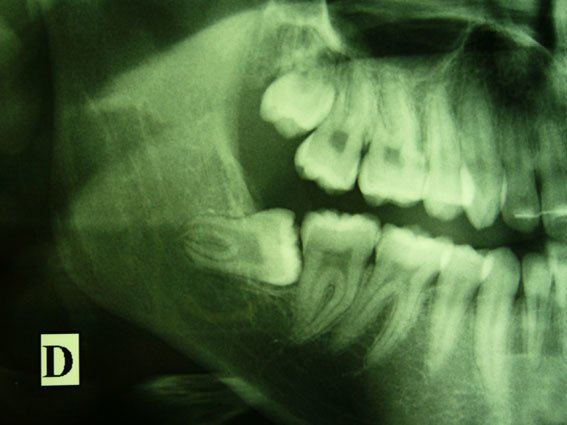

mate la dent de sagesse j'ai ça

et je refuse de me les faire extraire je flippe de l'opération

T’as dent de sagesse du haut pousse sur les autres. T’auras pas d’orthodontie si tu retire pas tes DS khey.

c'est pas de moi la photo, mes dents de sagesse du haut ont de la place je trouve, c'est les dents du bas qui sont comme la photo que j'ai mis au dessus